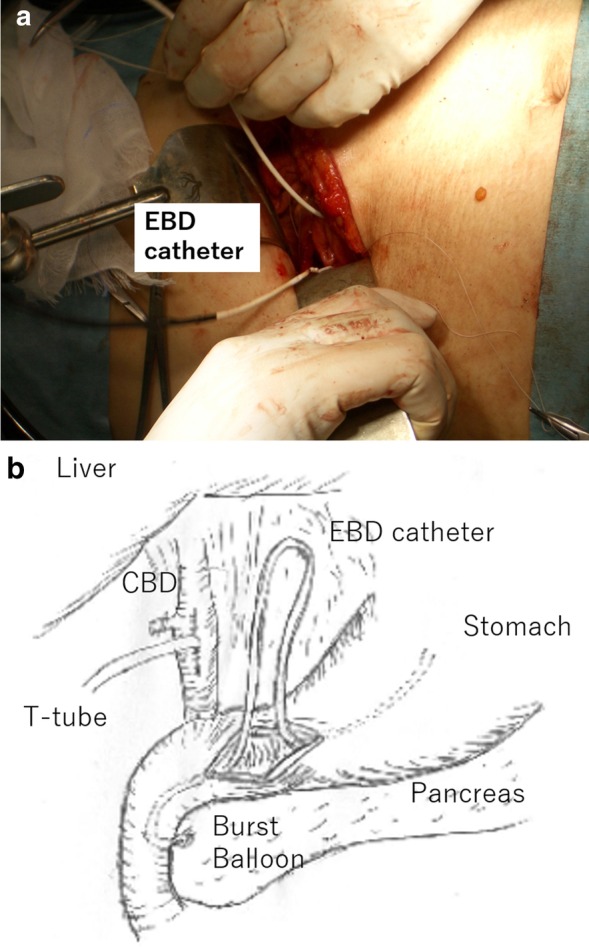

A 30-year-old woman was transported to our hospital by ambulance due to epigastric pain. A laboratory analysis revealed the following: white blood cells, 4000/mm3; total bilirubin, 3.0 mg/dL; alkaline phosphatase, 640 IU/L; GOT, 395 IU/L; GPT, 746 IU/L; and amylase, 37 IU/L. Abdominal CT demonstrated multiple gallbladder (GB) stones without inflammation of the GB; the diameter of the common bile duct (CBD) was 10 mm. ERCP was performed under the suspicion of CBD stones. Bile duct cannulation was easily performed. Cholangiography revealed no apparent CBD stones. Although EBD is not routinely carried out in this situation, we carefully performed EBD due to the suspicion of CBD stones, and carefully taking the clinical course into consideration. Before the procedure, a dilatation balloon (Hurricane RX Rapid Exchange, Boston Scientific, MA, USA) was inflated as a precaution in order to check the condition of the balloon. The dilatation balloon was then passed over the guidewire and located at the site of the biliary sphincter. The balloon was inflated to 2 atmospheres of pressure. After the procedure, the balloon suddenly burst. We were unable to remove the EBD catheter because the balloon was caught at the biliary sphincter (Figs. 1, 2). A computed tomography (CT) scan showing the burst balloon located at the site of the biliary sphincter (Fig. 3). Finally, we had to perform surgical intervention to remove the EBD. We made an incision at the pylorus, and then we manually pulled the EBD catheter through this incision, as shown in Fig. 4a, b. The broken catheter was successfully removed without injuring the biliary sphincter. Cholecystectomy, CBD exploration, and then removal of the CBD stone were performed. A T-tube was inserted for drainage. Intra-operative cholangiography revealed no residual stones and no biliary sphincter abnormality (Fig. 5). The burst balloon of the EBD catheter is shown in Fig. 6. The patient was discharged without any complications after removal of the T-tube on post-operative day 14.

Regarding the surgical technique, we think that there were three important considerations in the surgical removal of the burst balloon of the EBD catheter that was trapped at the biliary sphincter. First, we made the incision at the pylorus to remove the catheter, based on the consideration that an incision at the 2nd portion of the duodenum would increase the risk of post-operative complications (e.g., duodenal stenosis or leakage). Second, we preformed cholecystectomy and intra-operative cholangiography because residual stones were present in the CBD. Third, we had to pay attention to biliary sphincter edema and dysfunction induced by the burst balloon. Thus, a T-tube was inserted into the CBD after CBD stone removal.